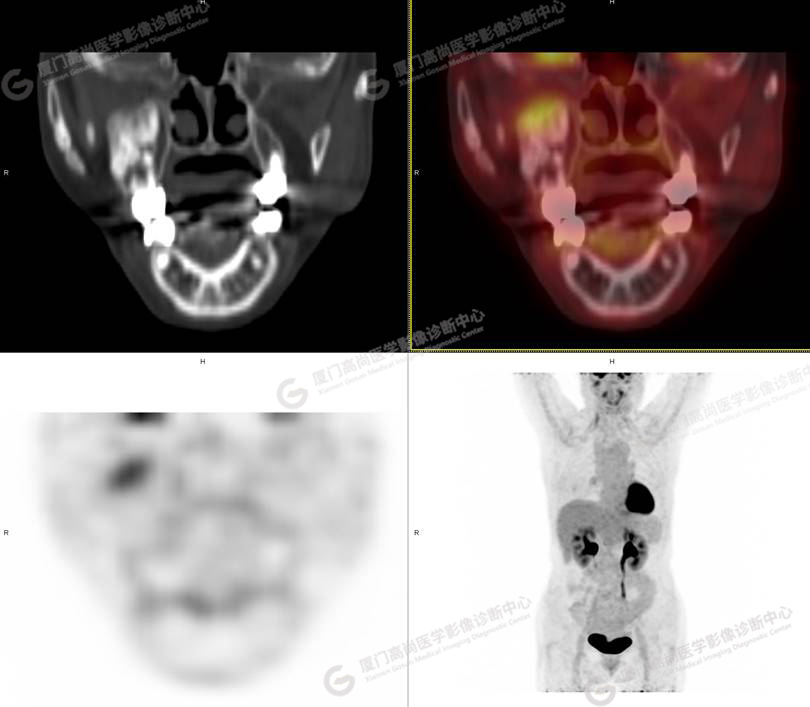

圖1

圖2

圖3

圖4

PET/CT檢查

PET/CT所見:右側(cè)上頜骨、右側(cè)顴骨及右側(cè)額骨骨質(zhì)膨脹,其內(nèi)密度不均勻性增高,部分放射性攝取輕微增高,SUVmax 2.27。